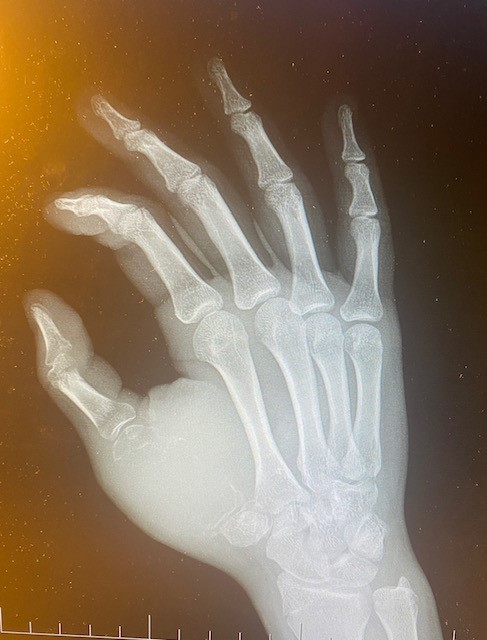

Vyšetrenia lekárov potvrdili jej dcére vážnu diagnózu zriedkavého nádoru krátkych kostí hornej končatiny s agresívnym rastom. Tento typ nádoru má nepredvídateľné správanie a môže metastázovať aj do pľúc. Zatiaľ čo rakovina kosti je závažným nádorovým ochorením, ktoré sa môže objaviť v akomkoľvek veku, s liečbou tohto typu nádoru u detí na Slovensku skúsenosti nemáme.

„Poistenke bola odporúčaná liečba v Českej republike na Klinike detskej onkológie Fakultnej nemocnice v Brne, keďže na Slovensku u detí v rámci tejto diagnózy liečba schválená nie je,“ hovorí o raritnom prípade závažnej diagnózy lekárka a podpredsedníčka predstavenstva VšZP Beata Havelková. Ďalšie vyšetrenia v Česku potvrdili obrovskobunkový nádor kostí s agresívnym rastom, kde dievčaťu hrozila dokonca amputácia ruky.

Schválená liečba trvala niekoľko mesiacov, nasledovalo vyšetrenie ruky a na výsledky, ktoré mali rozhodnúť o ďalšom postupe, už všetci netrpezlivo čakali. „Röntgen napokon priniesol dobré správy – nádor sa zmenšil a skalcifikoval. Tým sa však náš boj s touto diagnózou neskončil. Dcéra musela podstúpiť takmer šesťhodinovú operáciu na 1. Ortopedickej klinike vo Fakultnej nemocnici u Svätej Anny v Brne, počas ktorej jej transplantovali kosť v pravej ruke. Keď som napokon videla ten malý palček pravej ruky, ktorý vytŕčal spod sadry, vydýchla som si. Dcéra o ruku neprišla,“ spomína si na tieto dni jej mama.